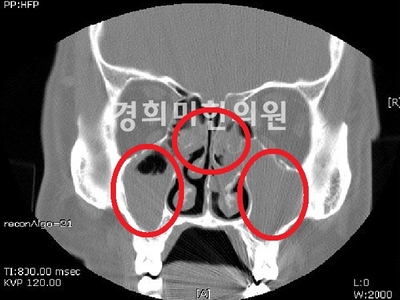

부비강염 CT 영상

편도염, 만약 급성 비염의 달기가 지나 2차 세균 감염되면 진한 노란색 콧물과 함께 코막히고 후비루가 심해집니다.더 악화되면 부비강염, 중이염, 인두편도염, 기관지염, 폐렴, 장염 등 다양한 합병증이 동반될 수 있습니다.이러한 합병증은 면역력이 떨어진 환자나 어린이에게서 호발하므로 주의가 필요합니다.